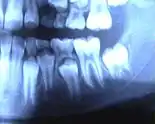

Панорамная рентгенограмма зубов: видны закладки постоянных зубов под прорезавшимися молочными, справа на схеме — белым окрашены молочные зубы, тёмные — закладка постоянных зубов в челюсти | ||

Наличие двух поколений (генераций) зубов свойственно большинству млекопитающих.

Первое поколение — молочные зубы, второе — постоянные.